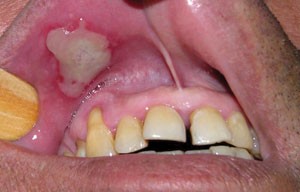

Sir, promoted by the paper by Gilvetti et al.,1 we would like to report a further case. A 50-year-old male was referred to our oral medicine clinic complaining of a painful ulcer on his upper lip. The patient reported a previous history of long-standing recurrent aphthous stomatitis (RAS) that had been treated elsewhere without relief of the symptoms, which had recurred nine days previously. In an attempt to alleviate the local pain he placed cotton wool soaked in formalin (37%) on his upper lip mucosa. Oral examination revealed a white pseudomembrane covering an extensive ulcer (2.5 × 2.5 cm diameter) with irregular borders. The lesion was associated with intense pain during mouth opening and lip palpation (Fig. 1) and was diagnosed as traumatic chemically induced oral ulceration. The patient was informed about the risks of self-treatment without professional advice and received instructions to maintain excellent oral hygiene. The mucosa injury completely resolved spontaneously after 21 days of clinical follow-up (Fig. 2).